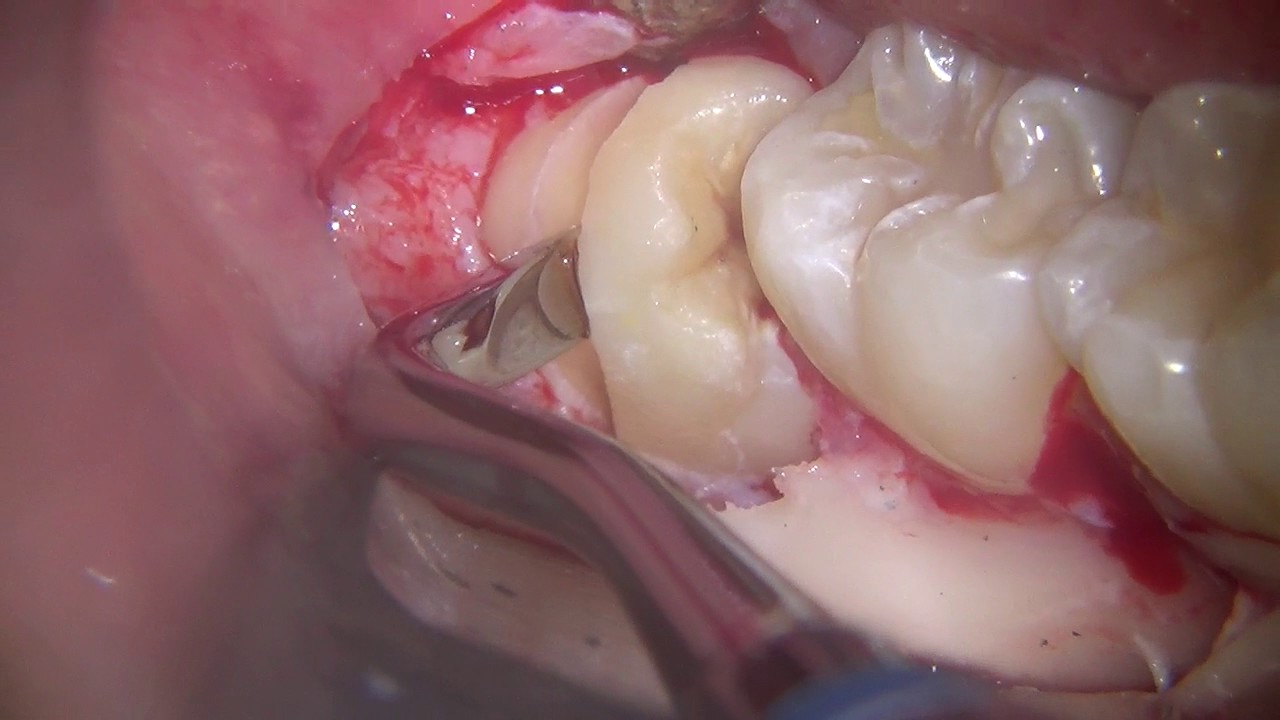

Informazioni Estrazione dente del giudizio inferiore. Lower third molar extraction

Microscope third molar extraction